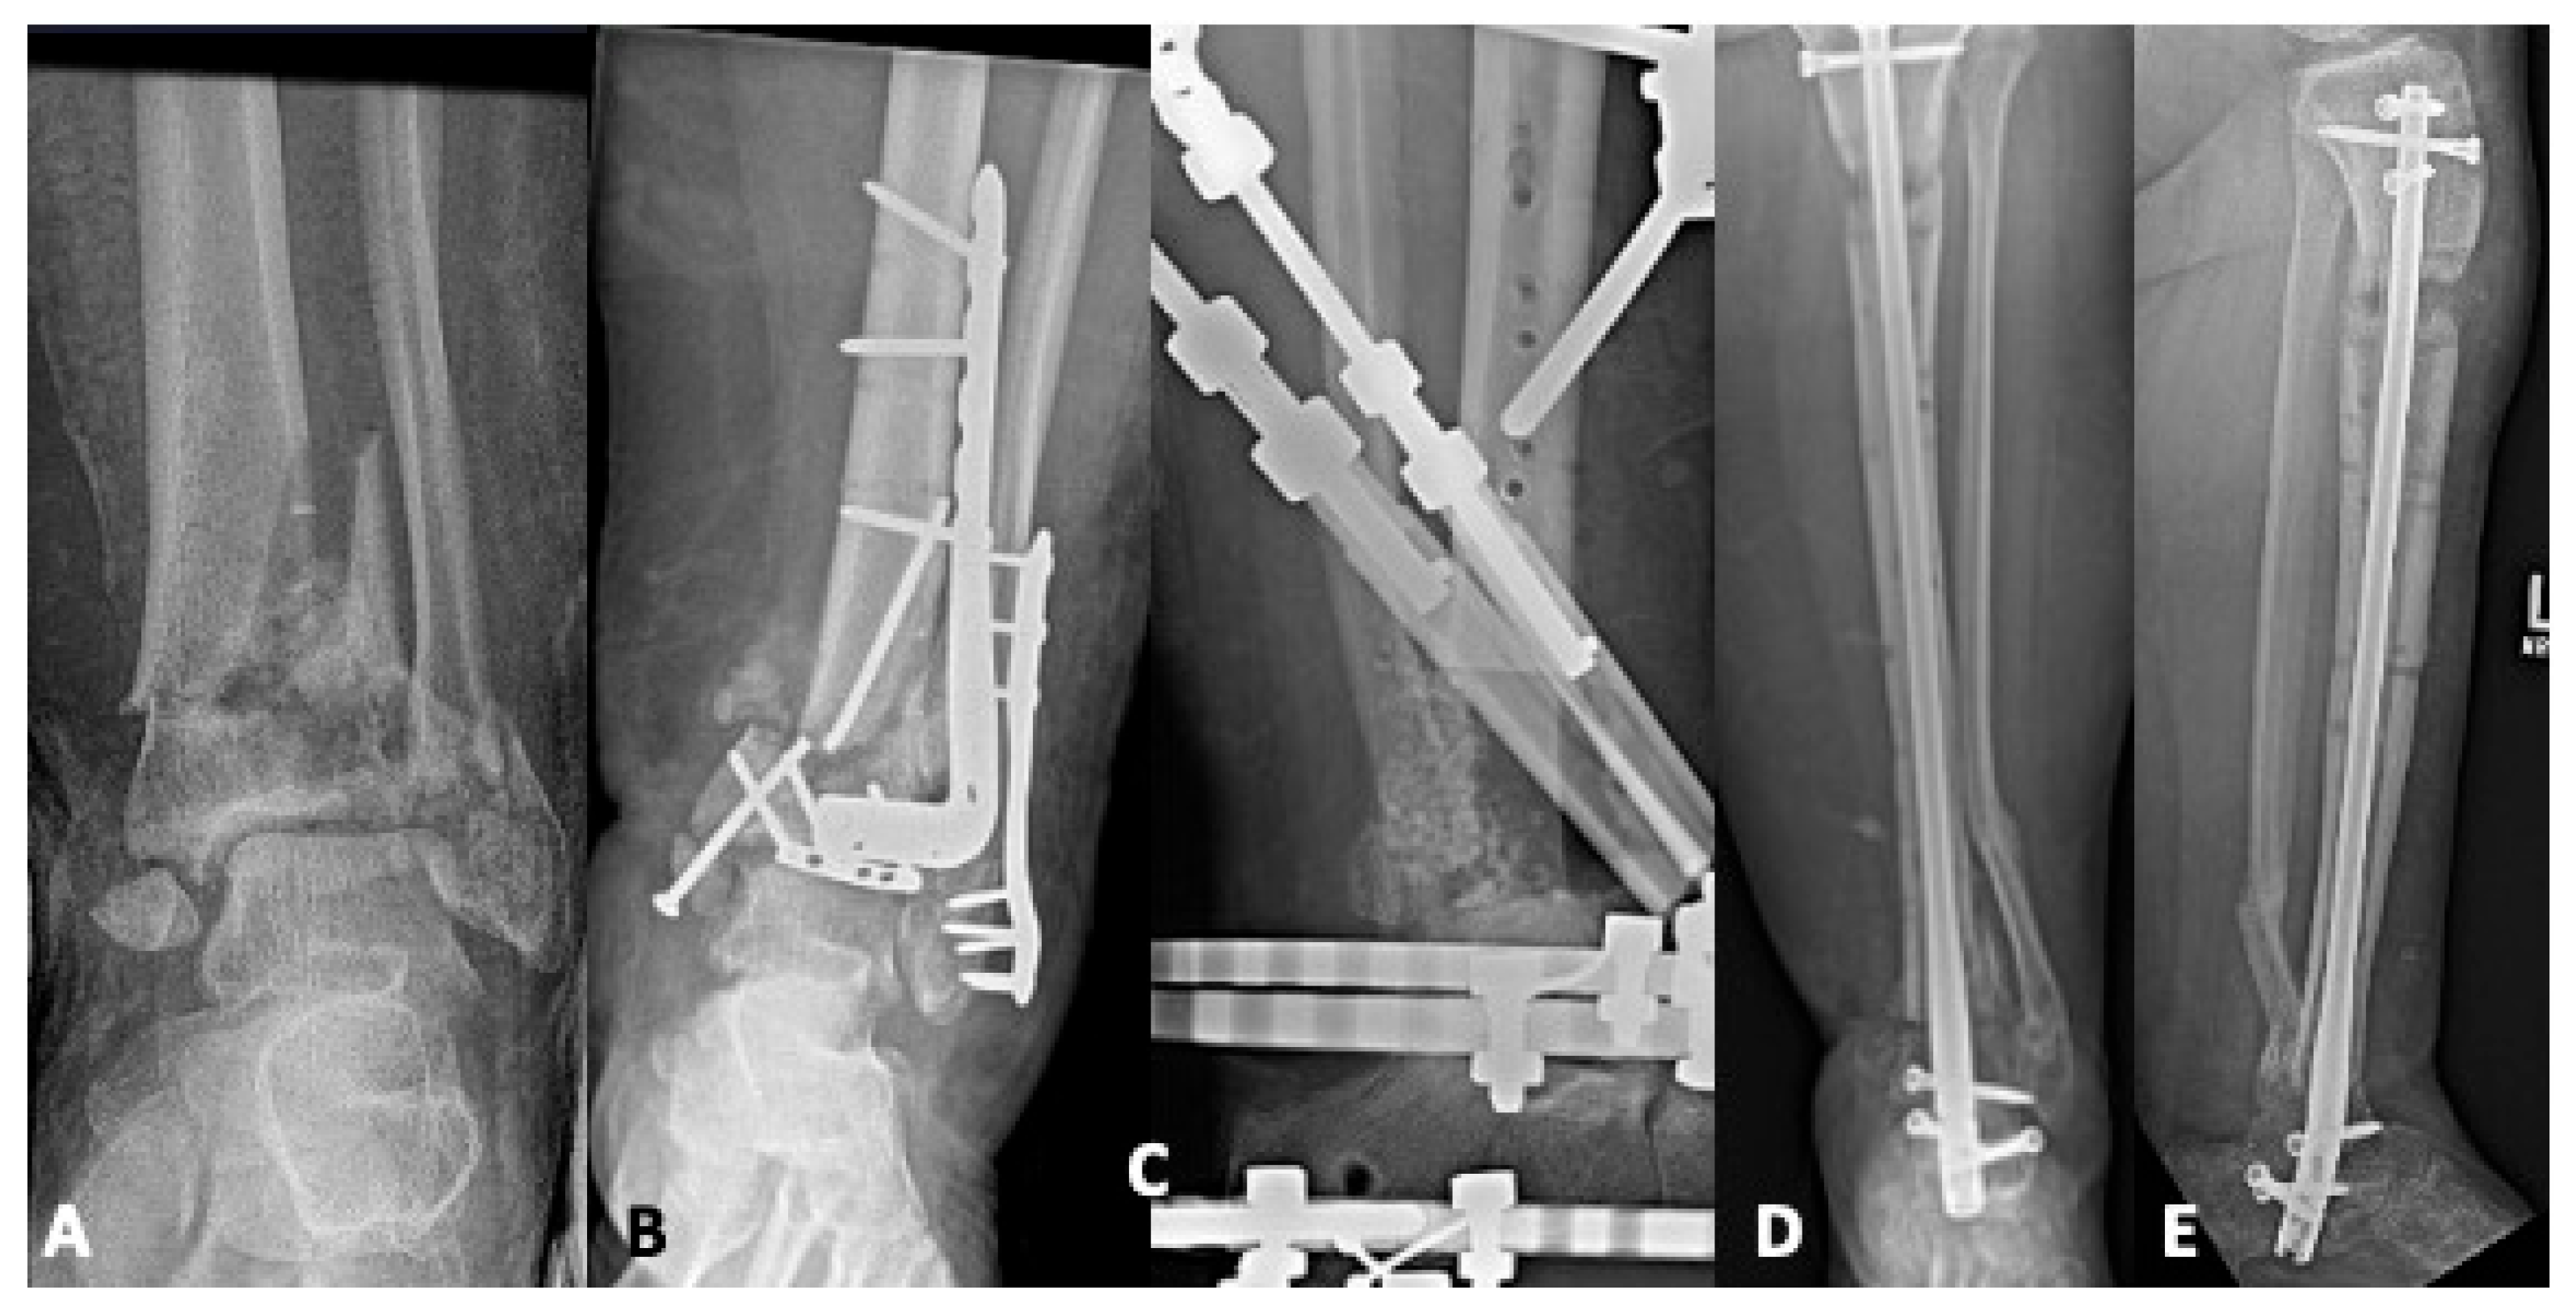

5.1. Revision Operative Fixation

5.2. Joint-Sacrificing Reconstruction

5.2.2. Tibiotalar Arthrodesis